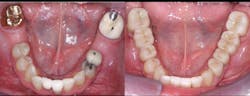

• Use resin-modified glass ionomer (RMGI) cement for zirconia restorations when the tooth preparations have near-optimum characteristics. See Figures 4 through 6 for examples of these characteristics. Most clinicians and researchers would agree that the tooth preparation should be at least 4 mm in height from the gingival margin to the occlusal table, and that the lack of parallelism of the preparation walls should be up to, but not more than, 20 degrees from the long axis of the tooth being prepared.

Figures 4-6: Images showing an adequate impression, the die of an adequate tooth preparation, and the resultant full-zirconia crowns.

Figure 4